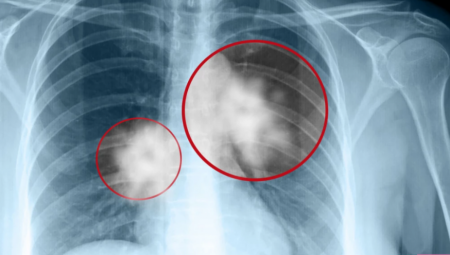

Tatjana Radosavljević kaže da vlažno vreme nema uticaj na sve pacijente koji imaju plućne bolesti, već samo na one koji imaju bronhijalnu astmu i hroničnu opstruktivnu bolest pluća.

- Oni reaguju na promenu vremena i na vlažnost u vazduhu isto kao kardiološki i reumatičari. Za razliku od astme i hronične opstruktivne bolesti pluća, ostala plućna oboljenja nisu toliko zavisna od promene vremena. Zato su se ovi pacijenti i javljali više lekarima Hitne pomoći. Čitavog dana je bila sparina. U nekim delovima grada je bila kiša. generalno je bio jako težak dan. Tako da je to razlog što se javljaju - kaže dr Tatjana Radosavljević.

- Pogoršava im se stanje u kom se nalaze. Postoji jedna razlika između astme i opstruktivne bolesti pluća. Astmatičari su između napad praktično zdrave osobe. Ovakvi uslovi, međutim, dovode do spazma i oni upadaju u astmatične napade, koji mogu čak da budu i produženi, da dođe do astmatičnog statusa. Oboleli od hronične opstruktivne bolesti pluća, inače, uvek imaju snižene kapacitete i spazam. Usled ovakvog vremena, takvo stanje im se samo pogoršava do one mere da ponekad moraju ne samo da zatraže pomoć Hitne, nego ponekad moraju da završe i u bolnicu pošto ne reaguju na terapiju - objasnila je ona.